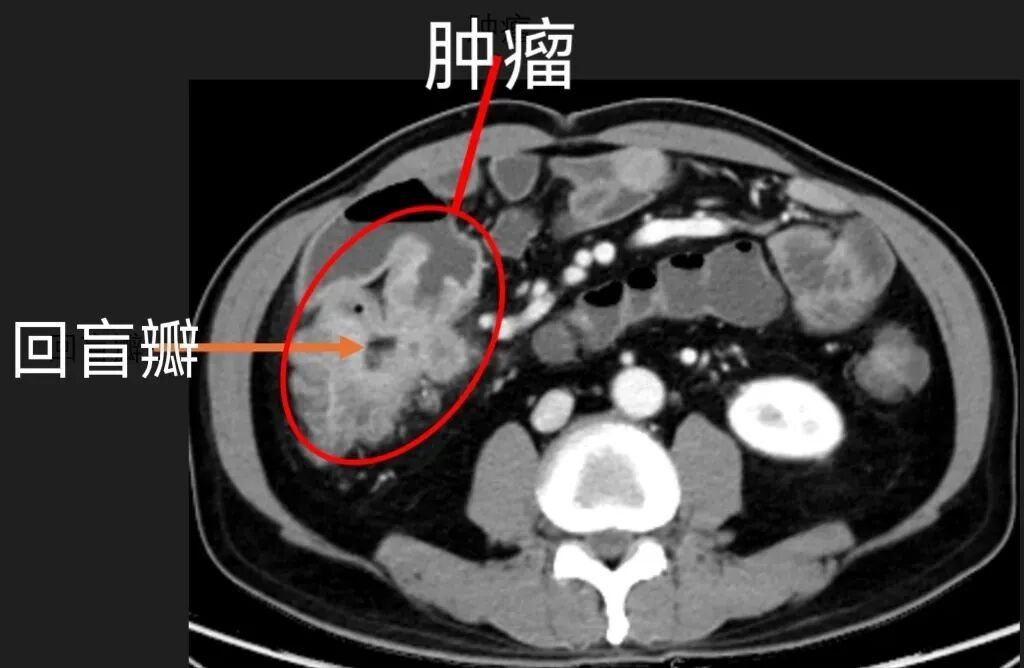

放射诊断科赵雪松副主任医师凭借多年丰富经验和细致观察,在张先生的CT上,敏锐发现关键隐患:一个巨大的病灶长在回盲部,回盲瓣变形了,这种位置的病变极易被误诊为普通炎症。更让人担忧的是,影像上肠壁的僵硬感、不均匀强化、周围淋巴结肿大,都指向了恶性肿瘤的可能。

△张先生的腹部CT

术中探查发现,张先生的腹腔存在轻度粘连,5×4cm大小的肿瘤位于回盲瓣的小肠侧,已侵犯肠壁外层,且与十二指肠紧密相邻,手术需格外精细精准。医生们凭借精湛医术,完成了肿块切除,同时完整保留了张先生的重要脏器功能。